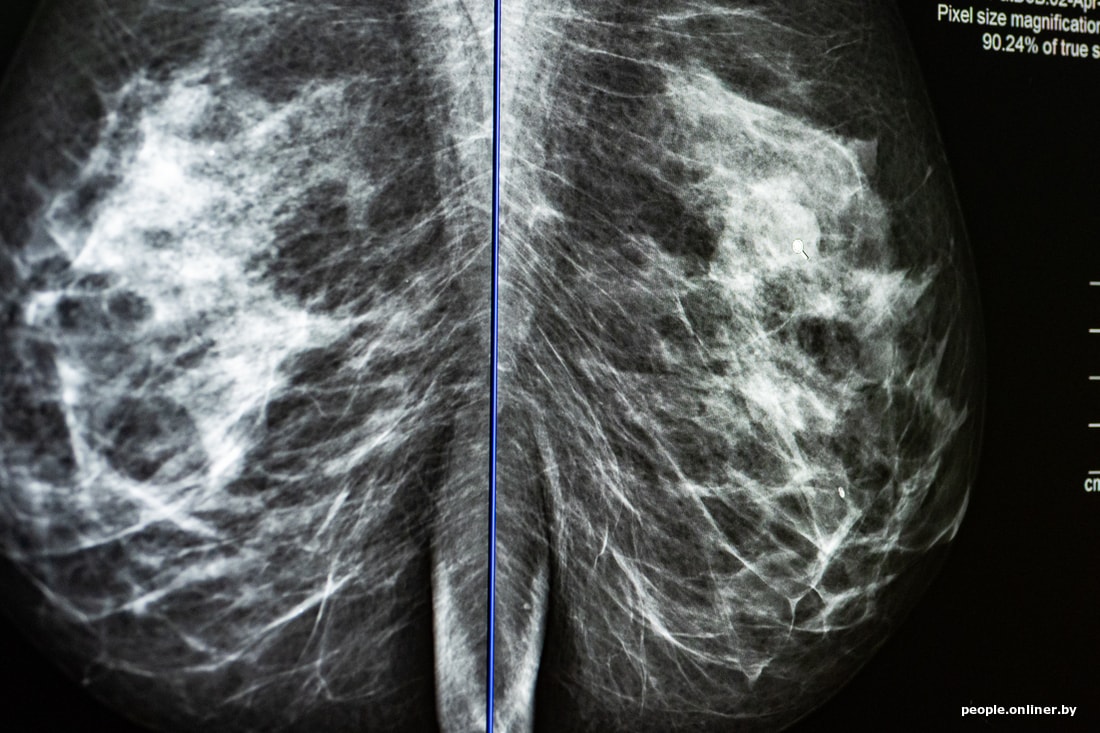

Врач-рентгенолог, специалист по маммографии медицинского центра «Лодэ» Анна Харун относится к раку с реалистичностью медика: «При скрининге мы не можем предотвратить рак, но можем обнаружить его вовремя».

— С помощью цифрового маммографа можно «играть» изображением: регулировать контрастность, яркость, то есть визуализация стала в разы лучше. Цифровые маммографы оснащены детекторами нового поколения, имеющими высокую разрешающую способность. Кроме того, появилась возможность архивировать изображения, осуществлять консультации сложных случаев дистанционно.

Смотрите сами. Оснащенность медицинских учреждений улучшилась. Количество маммографов и УЗИ-аппаратов в Минске выросло. Плюс женщины стали более внимательно относиться к своему здоровью. Не зря проводят Всемирный день борьбы с раком молочной железы и «розовый октябрь» — месяц борьбы с РМЖ. Конечно, свою роль сыграло появление новых опций у маммографов — это томосинтез (3D-визуализация) и контрастная томография (изображение 2D плюс элементы МРТ-диагностики).

— Женщина раздевается до пояса, снимает все украшения, подходит к аппарату и выкладывает грудь на подставочку. Ее высота регулируется в зависимости от роста. Далее лаборант прижимает грудь женщины, чтобы зафиксировать ее. Это нужно для того, чтобы молочная железа не двигалась во время исследования, а изображение было четким. Стандартная маммография включает в себя четыре проекции (по две на каждую железу). Процедура не болезненная, но немного чувствительная.